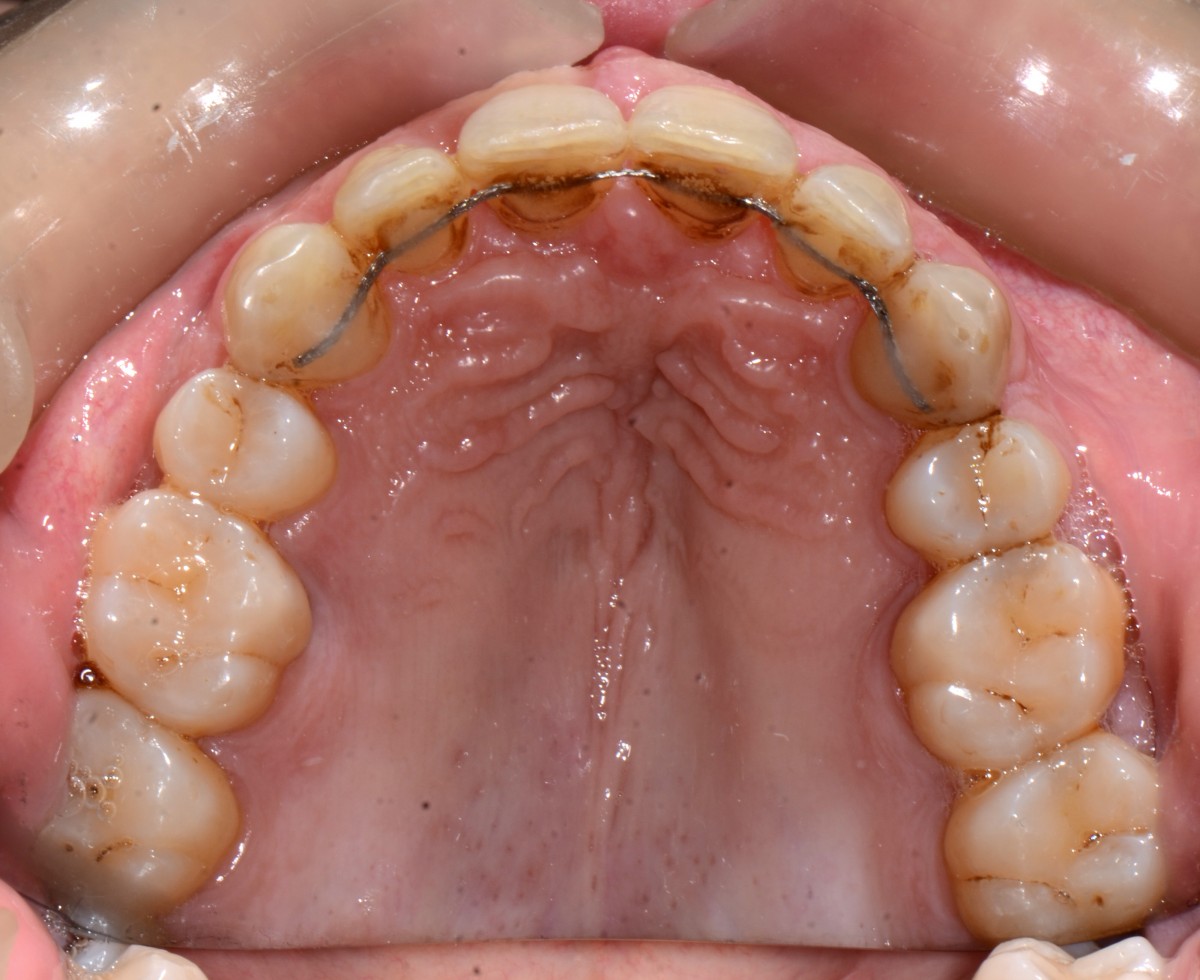

Treatment was planned with Clincheck® Software of Invis- align® (Milano, Italia). 36 aligners were prescribed for 40 weeks (9 months). Patient was monitored every 2 months with photos, oral hygiene mechani- cal cleaning and periodontic examination.

Lower teeth were proclined, upper and lower arches were slightly expanded and upper and lower anterior teeth were intruded to help opening the bite (fig. 9).

In this figure, patient during the Invisalign treatment. Note the perfect fit of the aligners due to correct planning and imple- mentation of biomechanics rules together with very com- pliant patient (figs. 10, 11).

All treatments’ goals were achieved in very short time and with maximum aesthetics during the treatment with his clear aligners providing him perfect cleaning access with predictable and accurate technology. Patient received fixed retain- ers for anterior teeth and re- movable clear aligners for night wear (figs. 17, 18).